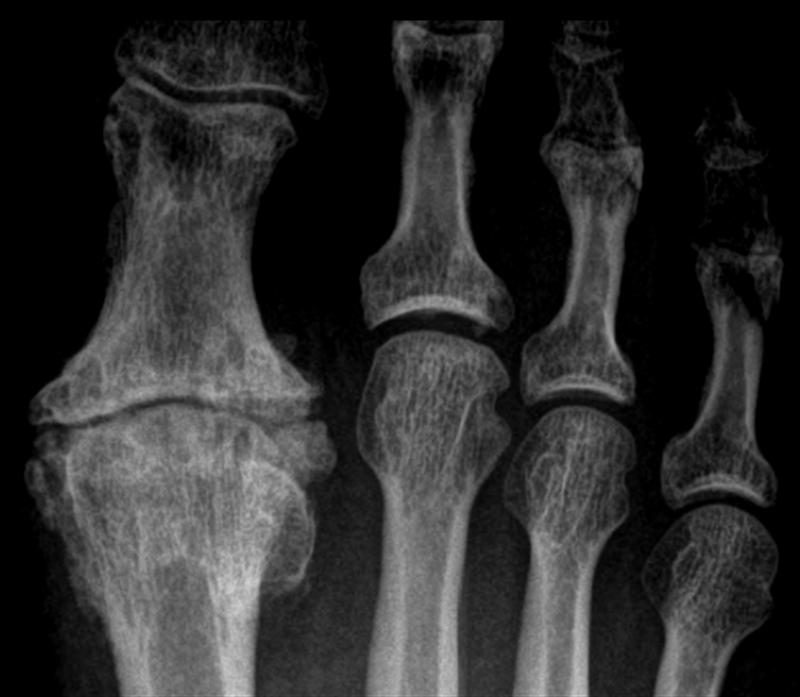

What Is Hallux Rigidus Of Foot . Hallux rigidus is a type of arthritis affecting the big toe's metatarsophalangeal (mtp) joint where the big toe meets the foot. It’s a type of degenerative arthritis that affects the joint where your big toe (hallux) attaches to your foot. Hallux rigidus is a disorder of the joint located at the base of the big toe. It is due to a wearing out. Hallux rigidus is arthritis of the joint at the base of the big toe. Hallux rigidus is a common foot condition characterized by pain and loss of motion of the 1st mtp joint in adults due to. Hallux rigidus causes stiffness in the big toe. It causes pain and stiffness in the joint, and with time, it gets. It is one of the most common arthritic conditions affecting people ages 30 to 60. Hallux rigidus (stiff big toe) occurs when the joint at the base of the big toe stiffens. It is the most common arthritic condition in the foot and can. It can be painful and affect standing and walking. It is the most common arthritic condition of the foot, affecting 1 in 40 people over the age of 50 and. This condition happens when the cartilage covering the ends of the bones in your. Hallux rigidus, is arthritis (pain and stiffening) of the main joint of the big toe in the ball of the foot.